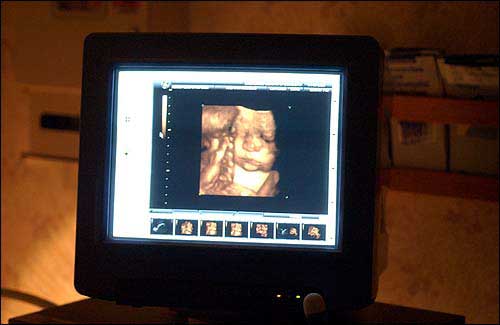

The Gisi baby, in his 37th week of gestation, is shown on the monitor via 3-D ultrasound.

A 3-D ultrasound image captured Thursday clearly revealed the face of Paul and Shawna Gisi’s son, who doesn’t have a name yet. His eyes, nose, mouth and chin were perfectly visible.

Paul and Shawna Gisi, Lawrence, look at an image of their baby boy with the help of sonographer Gayle Franklin. The technology behind Three-Dimensional Ultrasonography creates a more realistic image than ever for expectant mothers and their partners.